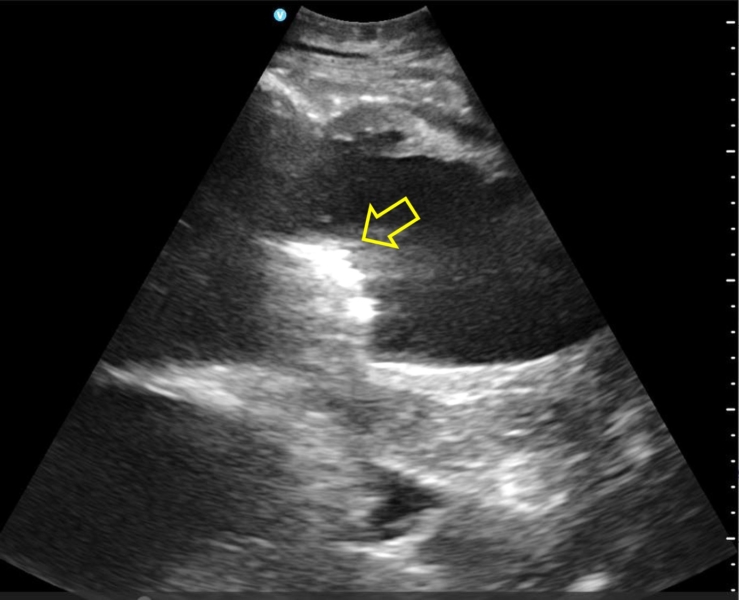

獣医学類5年生を対象に、北海道NOSAIオホーツク支所(遠軽・湧別・佐呂間診療所)の全面協力のもと、毎年恒例の「産業動物臨床実習」を開催しています。 ここは、教科書通りの答えがない、命と向き合う最前線の現場です。

この実習の最大の特徴は、現場で働く獣医師の先生方から、マンツーマンで直接指導を受けられることです。 実際の症例を前に、どのように診断し、治療の決断を下すのか。プロの技術と情熱を間近で感じる経験は、学生にとって何にも代えがたい財産となります。 参加した学生からは「非常に勉強になった」「改めて大動物臨床の道に進みたくなった」という声が毎年寄せられ、本学を象徴する実習の一つとなっています。